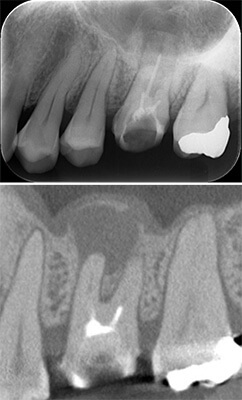

事故により上の前歯がなくなってしまいました。そのままインプラントをするのではなく、矯正治療により歯並びの改善をすることが、インプラントの予後を改善するポイントです。噛み合わせが悪いままインプラントをするとインプラントが後々トラブルを起こすことがあります。

インビザラインによる矯正治療後にインプラント治療を行い、治療終了。先天欠損であった右下の前歯は接着ブリッジによる治療を行いました。

抜歯に伴う骨欠損が大きい場合は、大規模な骨増生が必要になることがあります。